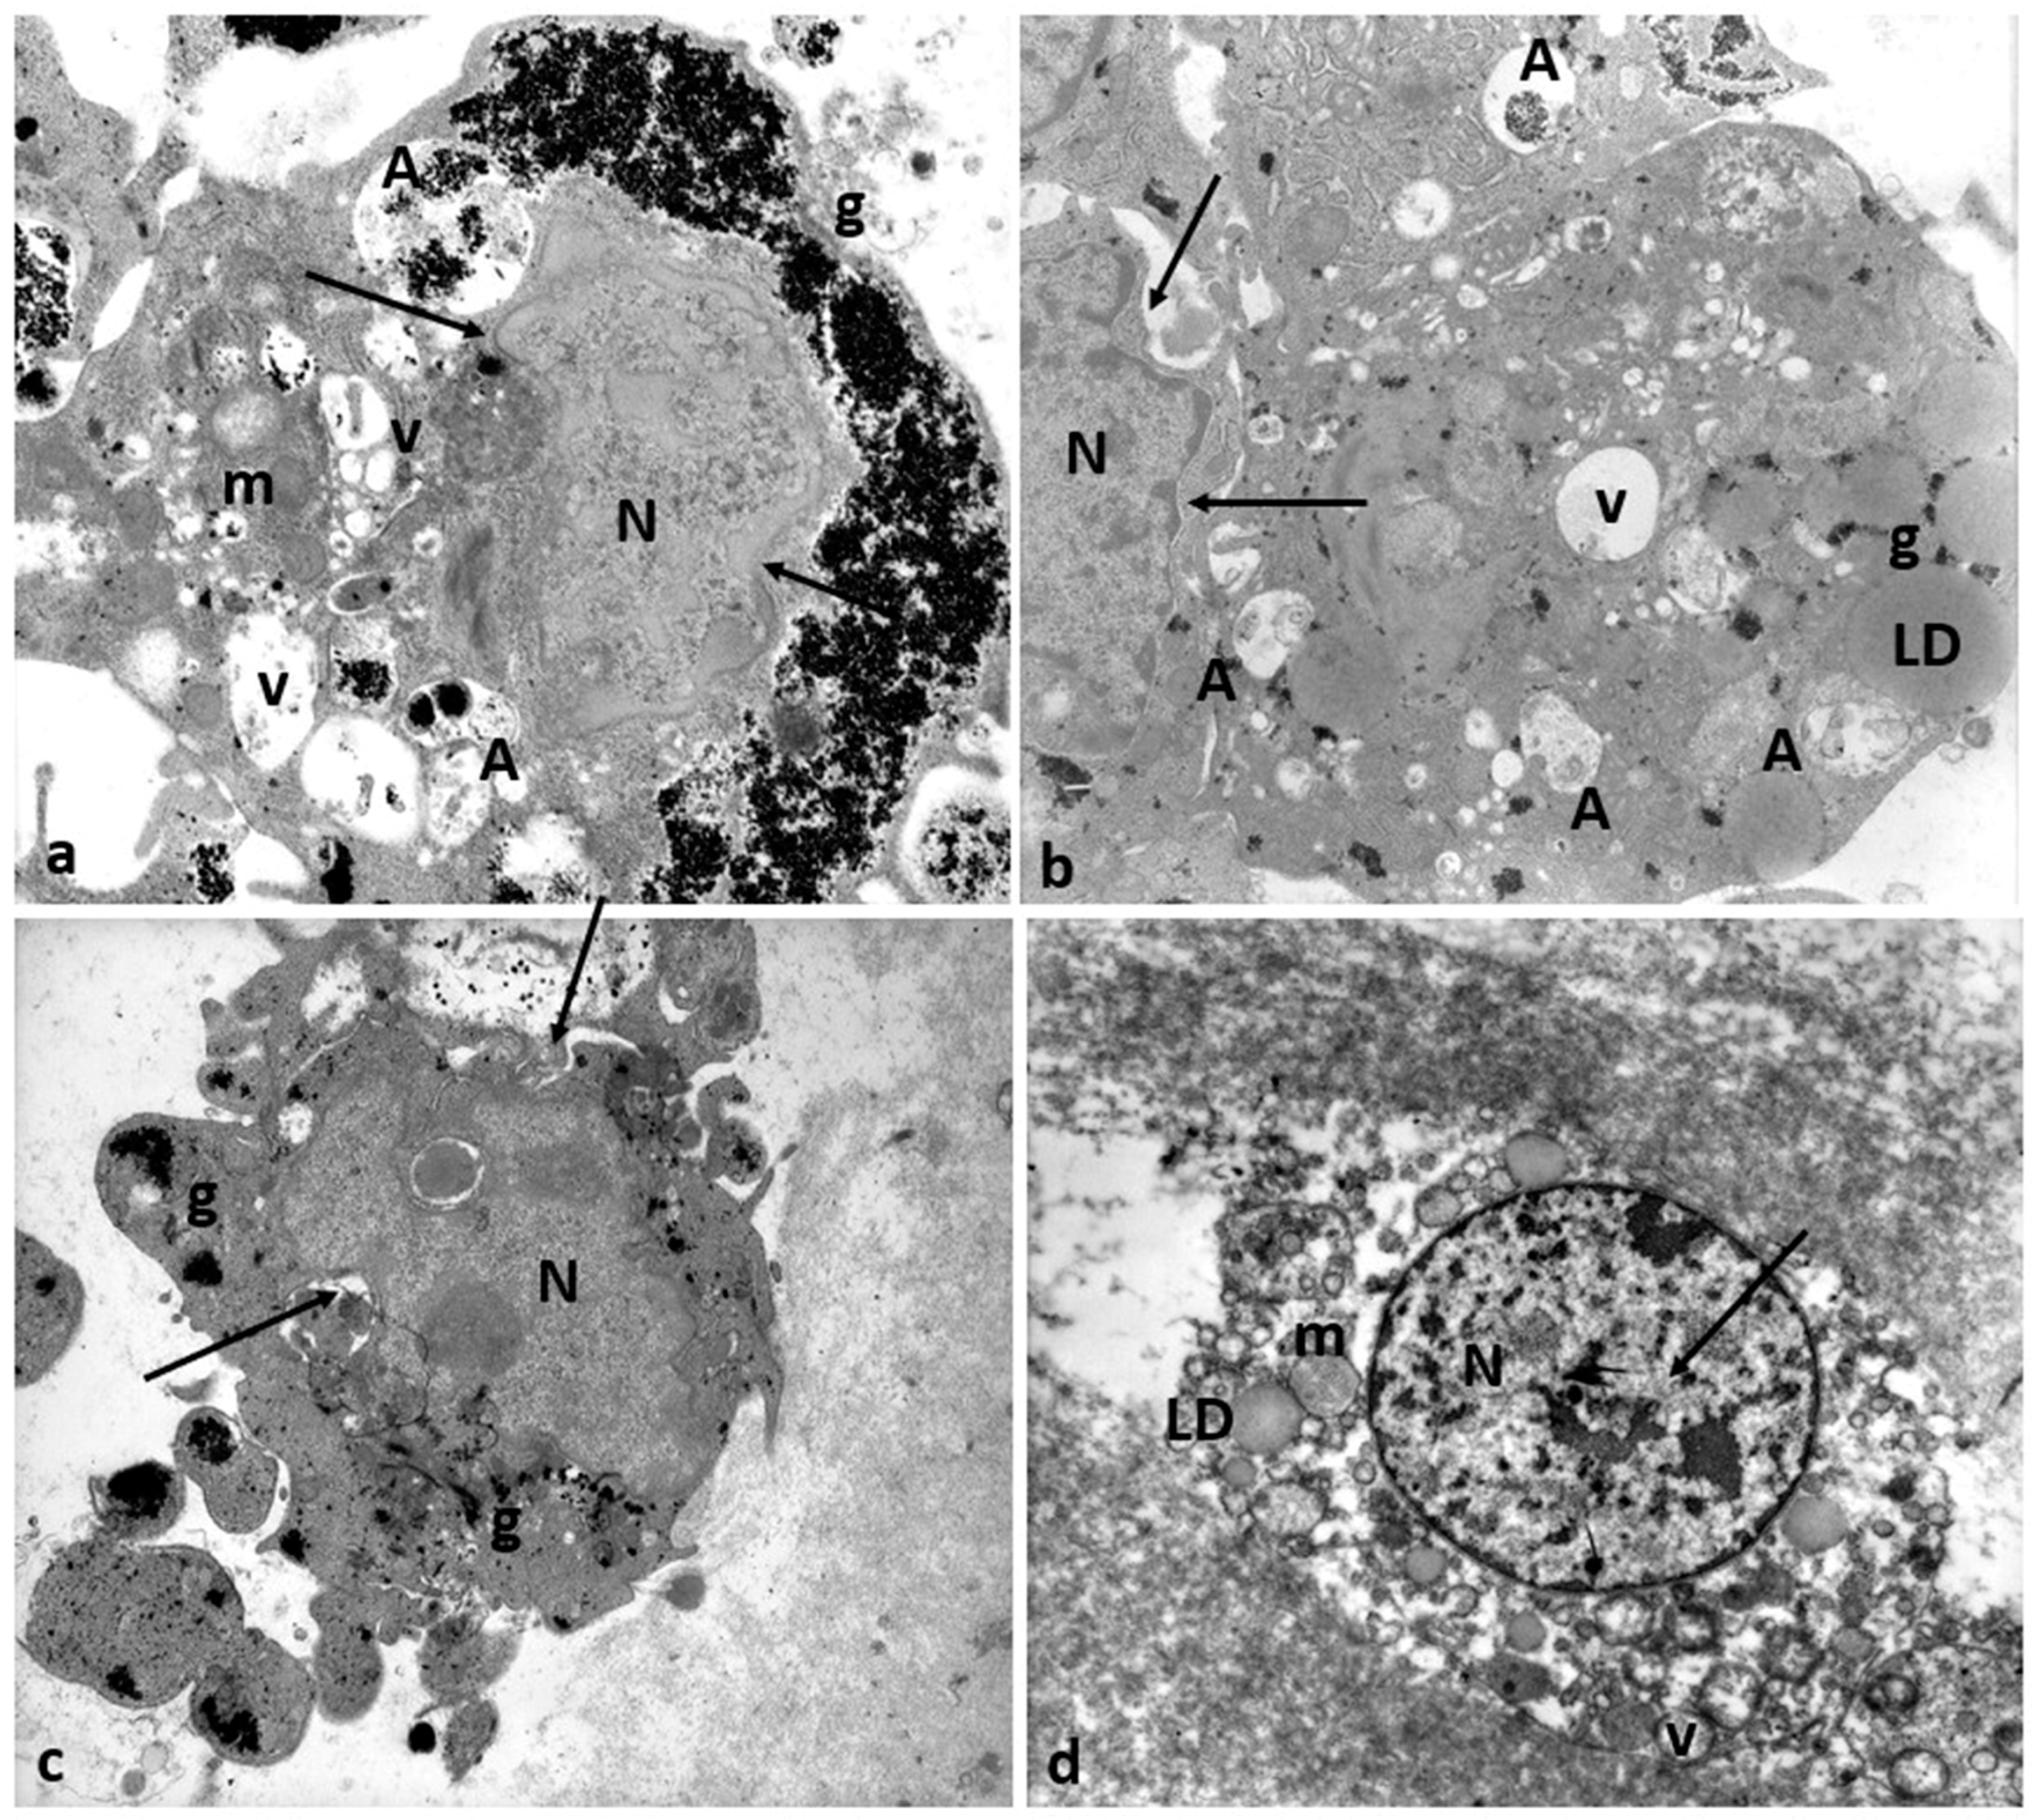

In 28.6% of the Group 2 patients (2/7), CCs showed even characteristic apoptotic signs (Figure 9a, tick arrows, and Figure 11).

Regressing and degenerating CCs in Group 2 patients. (a–c) Numerous vacuoles (V) and autophagosomes (A) containing involuting organelles occur in the cytoplasm. Note the presence of abundant glycogen granules (g) peripherally accumulating around the nucleus (N) or inside vacuoles, cytoplasmic fragments, and cellular blebs. (d) Evidence of cytoplasmic lysis and vacuolization. Nuclear alterations occur (arrows). m, mitochondria; LD, lipid droplets. Bar = 35 µm.

Figure 11 shows degenerating CCs in Group 2 patients. Numerous regressing elements such as vacuoles of different sizes and autophagosomes containing glycogen granules and involuting mitochondria are present (Figure 11a–c); cytoplasmic fragments deriving from cellular blebbing (Figure 11c), pyknotic (Figure 11c) or regressing nuclei (Figure 11a–c), and a dense or lysed, vacuolized cytoplasm (Figure 11d) were observed.